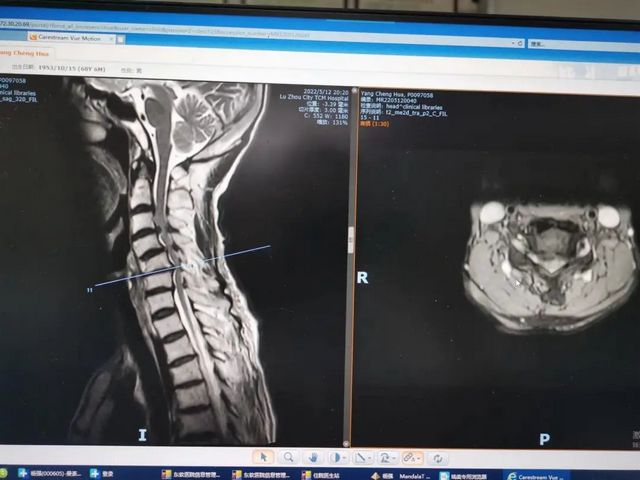

杨先生腰椎管狭窄症拍片

杨先生脊髓性颈椎病拍片